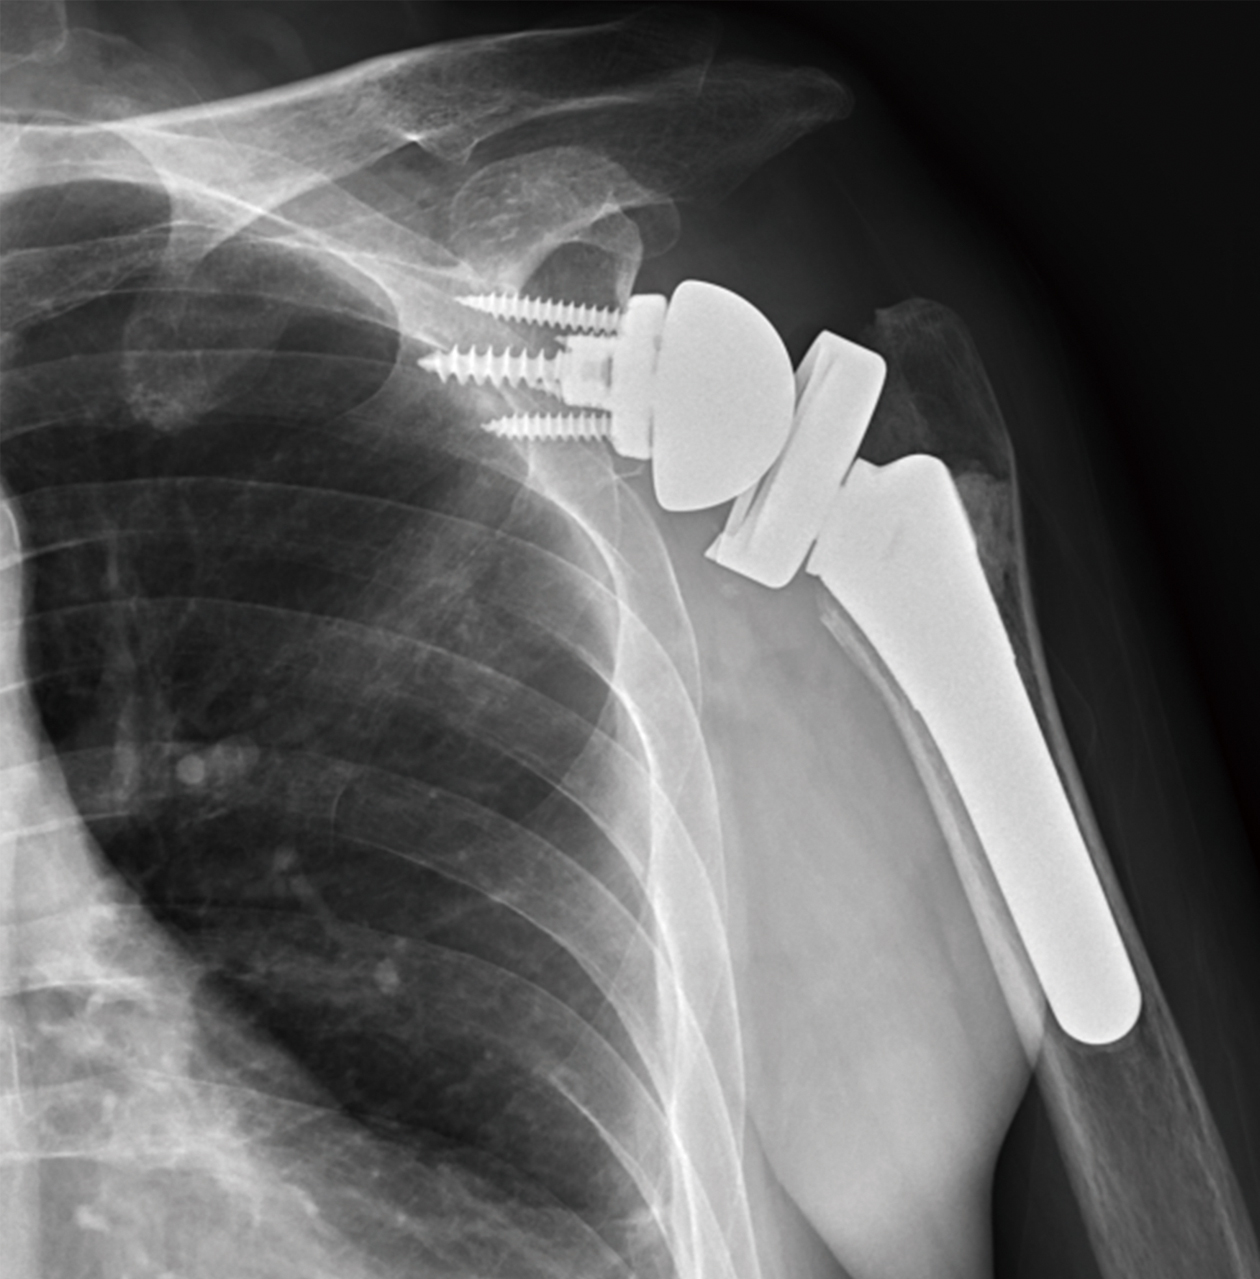

謝陳女士74歲,右肩關節疼痛一年以上,活動受限,手臂無力上舉,經檢查發現右肩關節炎,旋轉肌腱大片全層破裂內縮,接受反置式人工全肩關節置換術,術後疼痛緩解,活動角度可達140度以上。

右肩關節炎合併旋轉肌腱斷裂,經反置式人工全肩關節置換手術治療。